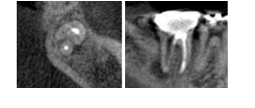

Anatomical variations

Prevention

Radiographs should be used to give you an idea about the anatomy of the tooth and possible variations.

CBCT is very useful for identifying complex anatomy.

Ultrasonic tips are helpful in locating hidden canals in a complex anatomy.